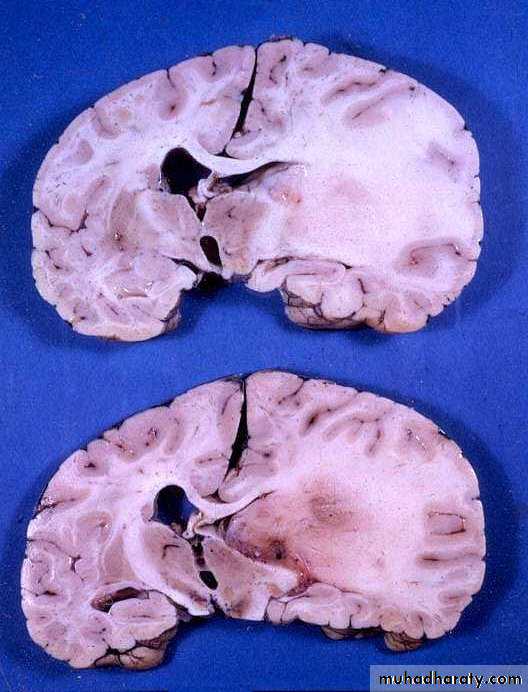

Metastatic Brain Tumours• Constitute 15% of intracranial tumours.

• The commonest sites of origin are the lung (40%) and breast (10-30%), in addition to melanoma (5-15%), kidney and colon.

• In 15% of cases, a primary source is never found.